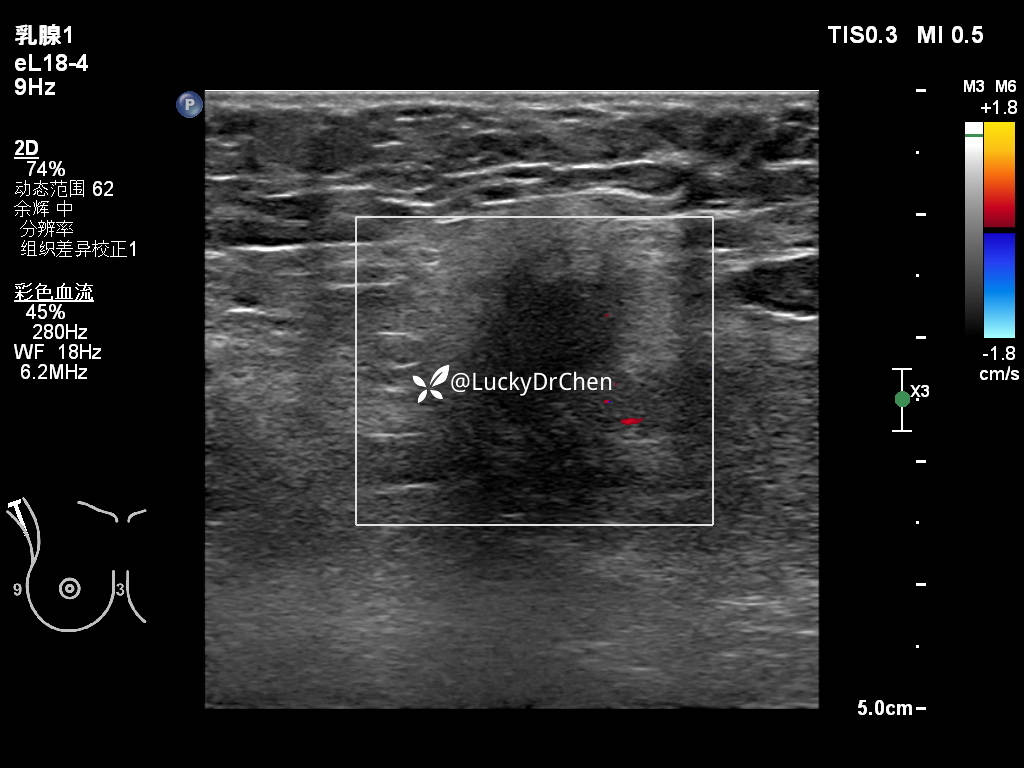

脂肪层血流信号增多